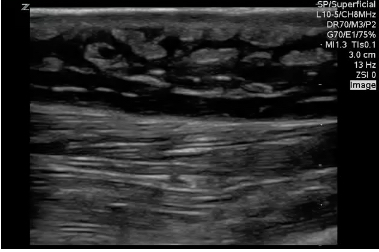

CEllulitis - CobbleStoning

Abscess

Evidence: https://bmjopen.bmj.com/content/7/1/e013688

Tutorial: http://5minsono.com/softtissue/